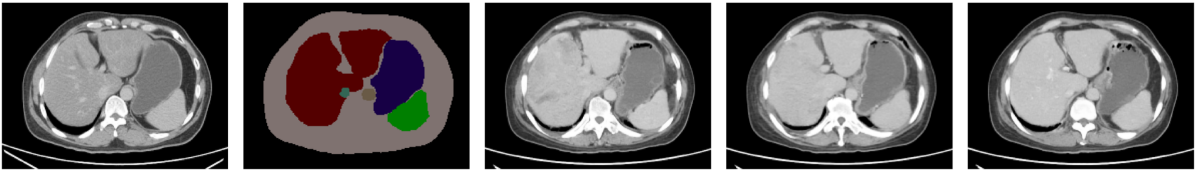

Comparison study. We carried out a quantitative evaluation of the diffusion models against other SOTA algorithms such as Pix2Pix, OASIS, SPADE, and SDM methods. In terms of image quality metrics such as FID, PSNR, and SSIM, the diffusion models outperformed non-diffusion-based methods. However, in terms of learned correspondence metrics like DSC, diffusion models surpassed other models for larger organs such as the liver, spleen, and kidneys. The OASIS method achieved superior performance for relatively small organs and structures like gallbladder and left adrenal gland. This may be because OASIS was good at synthesizing the clear boundary between small organs and the background, resulting in better segmentation results by TS and thus having higher DSC scores. Fig. 4 presents multiple results ranging from the lower to the upper abdomen, from different methods. It is worth noting that from the top row of Fig. 4 GAN-based methods struggled to synthesize images when the number of mask classes was sparse. For example, Pix2Pix and SPADE were unable to generate realistic images. OASIS generated an image from the upper abdomen, which was inconsistent with the location of the given mask. The bottom row illustrated the same trend. GAN-based models failed to synthesize the context information within the body mask, for example, the heart and lung. On the contrary, diffusion models including the SDM model succeed to generate reasonable images based on the given masks. One explanation was that diffusion models were more effective when the number of masks decreased and the corresponding supervision became sparser.

Figure 4: Results from different semantic image synthesis methods. The color map for different organs: body (beige), spleen (green), liver (dark red), right kidney (blue), left kidney (yellow), stomach (indigo), aorta (light brown), duodenum (light purple), pancreas (gray), right/left adrenal gland (dark/light green), inferior vena cava (aqua blue green), bladder (shallow brown), prostate (purple).